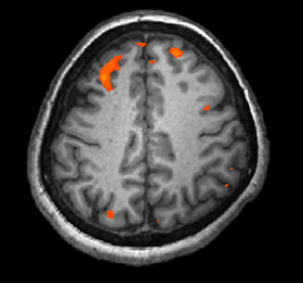

Three brain-imaging scans are shown.

Figure 3.1 Different brain imaging techniques provide scientists with insight into different aspects of how the human brain functions. Left to right, PET scan (positron emission tomography), CT scan (computerized tomography), and fMRI (functional magnetic resonance imaging) are three types of scans. (credit “left”: modification of work by Health and Human Services Department, National Institutes of Health; credit “center”: modification of work by “Aceofhearts1968″/Wikimedia Commons; credit “right”: modification of work by Kim J, Matthews NL, Park S.)